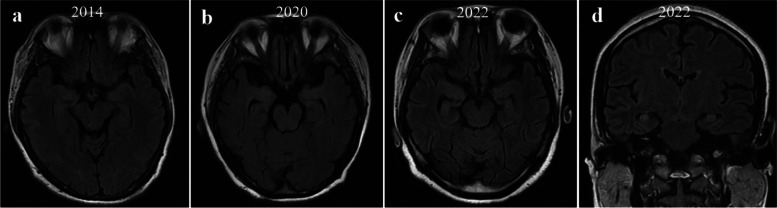

Case presentation: We report a Chinese female patient diagnosed with anti-NMDAR encephalitis. Over the past 30 years, the patient had experienced eight episodes with seizures as the first symptom, which eventually progressed to autoimmune-associated epilepsy. In the last two episodes, both serum and cerebrospinal fluid of the patient were negative for AE-related antibodies, and brain magnetic resonance imaging (MRI) revealed abnormal hyperintensity in the bilateral hippocampi. The patient's symptoms were poorly controlled by immunotherapy but well controlled by anti-seizure medicines.

Conclusions: Patients with a long history of AE and multiple relapses that start with seizures may display alterations of brain structure. Physicians should pay attention to autoimmune-associated epilepsy.